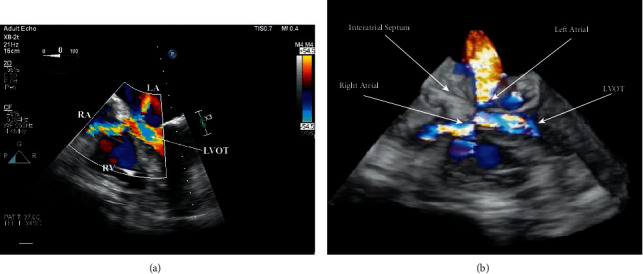

The Gerbode defect was first described in the late 1950s as a congenital peri-membranous ventricular septal defect (VSD), resulting in a left to right ventriculoatrial shunt. We present a case of a patient with restenosis of a prior bioprosthetic aortic valve (AV) who underwent reoperative AV replacement (AVR), which was complicated by a unique iatrogenic Gerbode defect with concurrent LV-LA communication. Our case highlights the unique complications resulting from ventriculoatrial shunts, with consideration paid to the management of ventriculoatrial defects described.